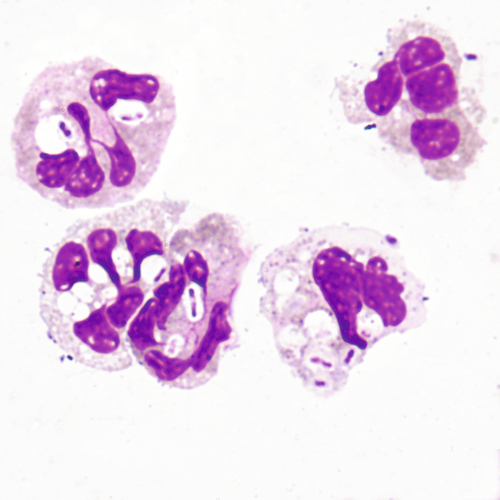

Mitotic figures may be found in normal fluids and are not necessarily an indication of malignancy. The size of this mitotic figure, however, is quite large, and malignant cells were easily found.